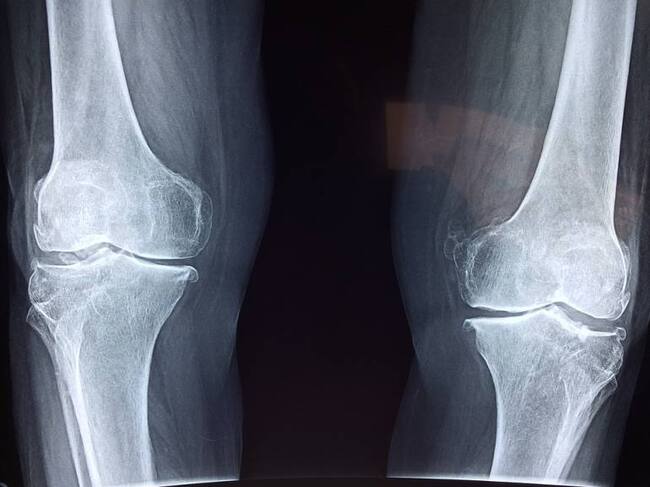

(C.C Google Images Pixabay)